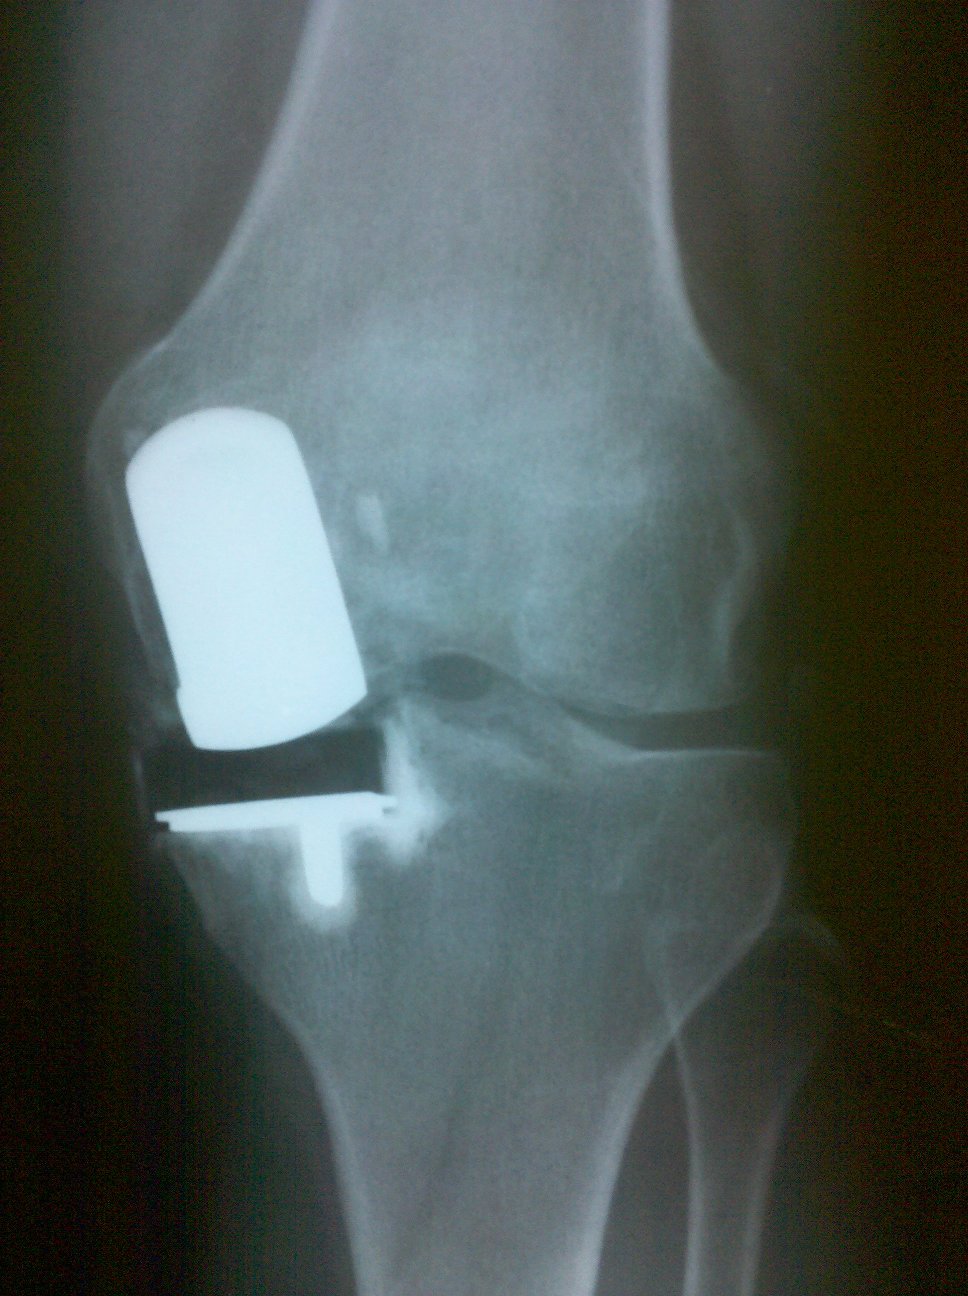

Middle aged female 5 years s/p unicondylar replacement who was able to hike the Virgina Appalachian Trial.

- Vanguard Biomet Knee

- Repicci Unicondylar Replacement